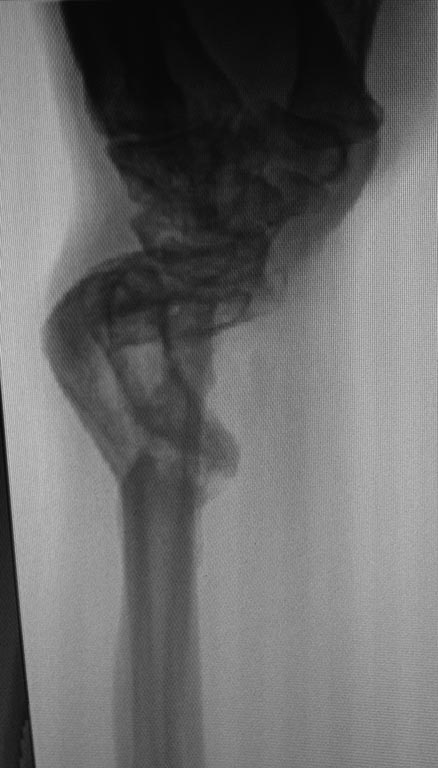

Последствие огнестрельного перелома костей предплечья |

Пациент получил огнестрельное ранение левого предплечья с переломом обеих костей в нижней трети в августе 2014г. Первоначально лечился в аппарате Илизарова. Со слов пациента, в связи с развитием ИО в область проведения спиц аппарат демонтирован, продолжено лечение в повязке.

В настоящее время в области левого предплечья множественные окрепшие послеоперационные рубцы, отмечается деформация в виде выстояния головки локтевой кости, формирования гипертрофической костной мозоли лучевой кости. Рентгенограммы прилагаю.

Основная жалоба - ограничение супинации, которое мешает выполнять работу.